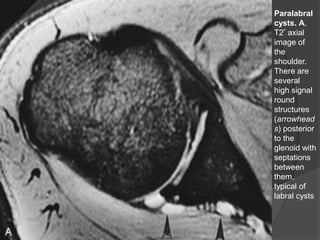

Paralabral

cysts. A,

T2* axial

image of

the

shoulder.

There are

several

high signal

round

structures

(arrowhead

s) posterior

to the

glenoid with

septations

between

them,

typical of

labral cysts

Lesões Labiais Não

Relacionadas a Instabilidade

 Cistos Paralabiais:

 A água é reabsorvida do cisto, com a

permanência de um material proteináceo

espesso.

 As imagens por RM mostram uma massa

redonda ou oval multiloculada de baixa

intensidade de sinal em T1 e alta

intensidade em T2.